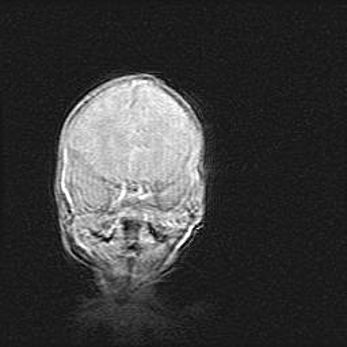

Открытая гидроцефалия.

Возраст: 9 месяцев 12 дней

Вес: 6800 г

Пол: мужской

Окружность головы: 41,5 см

Срок гестации: 28 недель

Гидроцефалия головного мозга у новорожденных имеет характерный признак: опережающий рост окружности головы приводит к визуально хорошо определяемой гидроцефальной форме сильно увеличенного в объёме черепа. Детские неврологи определяют следующие симптомы гидроцефалии у грудничков: выбухающий напряжённый родничок, частое запрокидывание головы, смещение глазных яблок к низу.